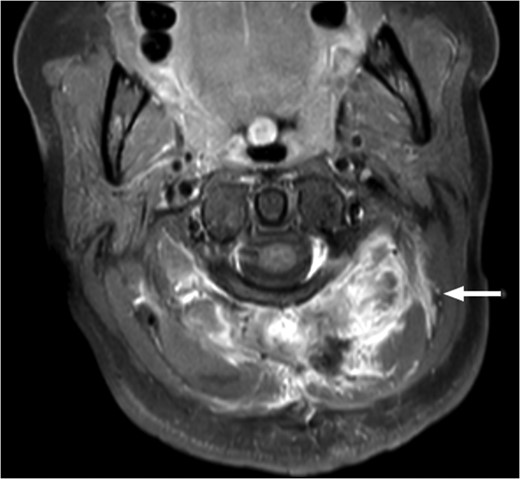

T1-weighted MRI showing the lesion in the posterosuperior aspect of the left neck arising at the level of C1, eroding through the C1 vertebra and displacing the thecal sac.